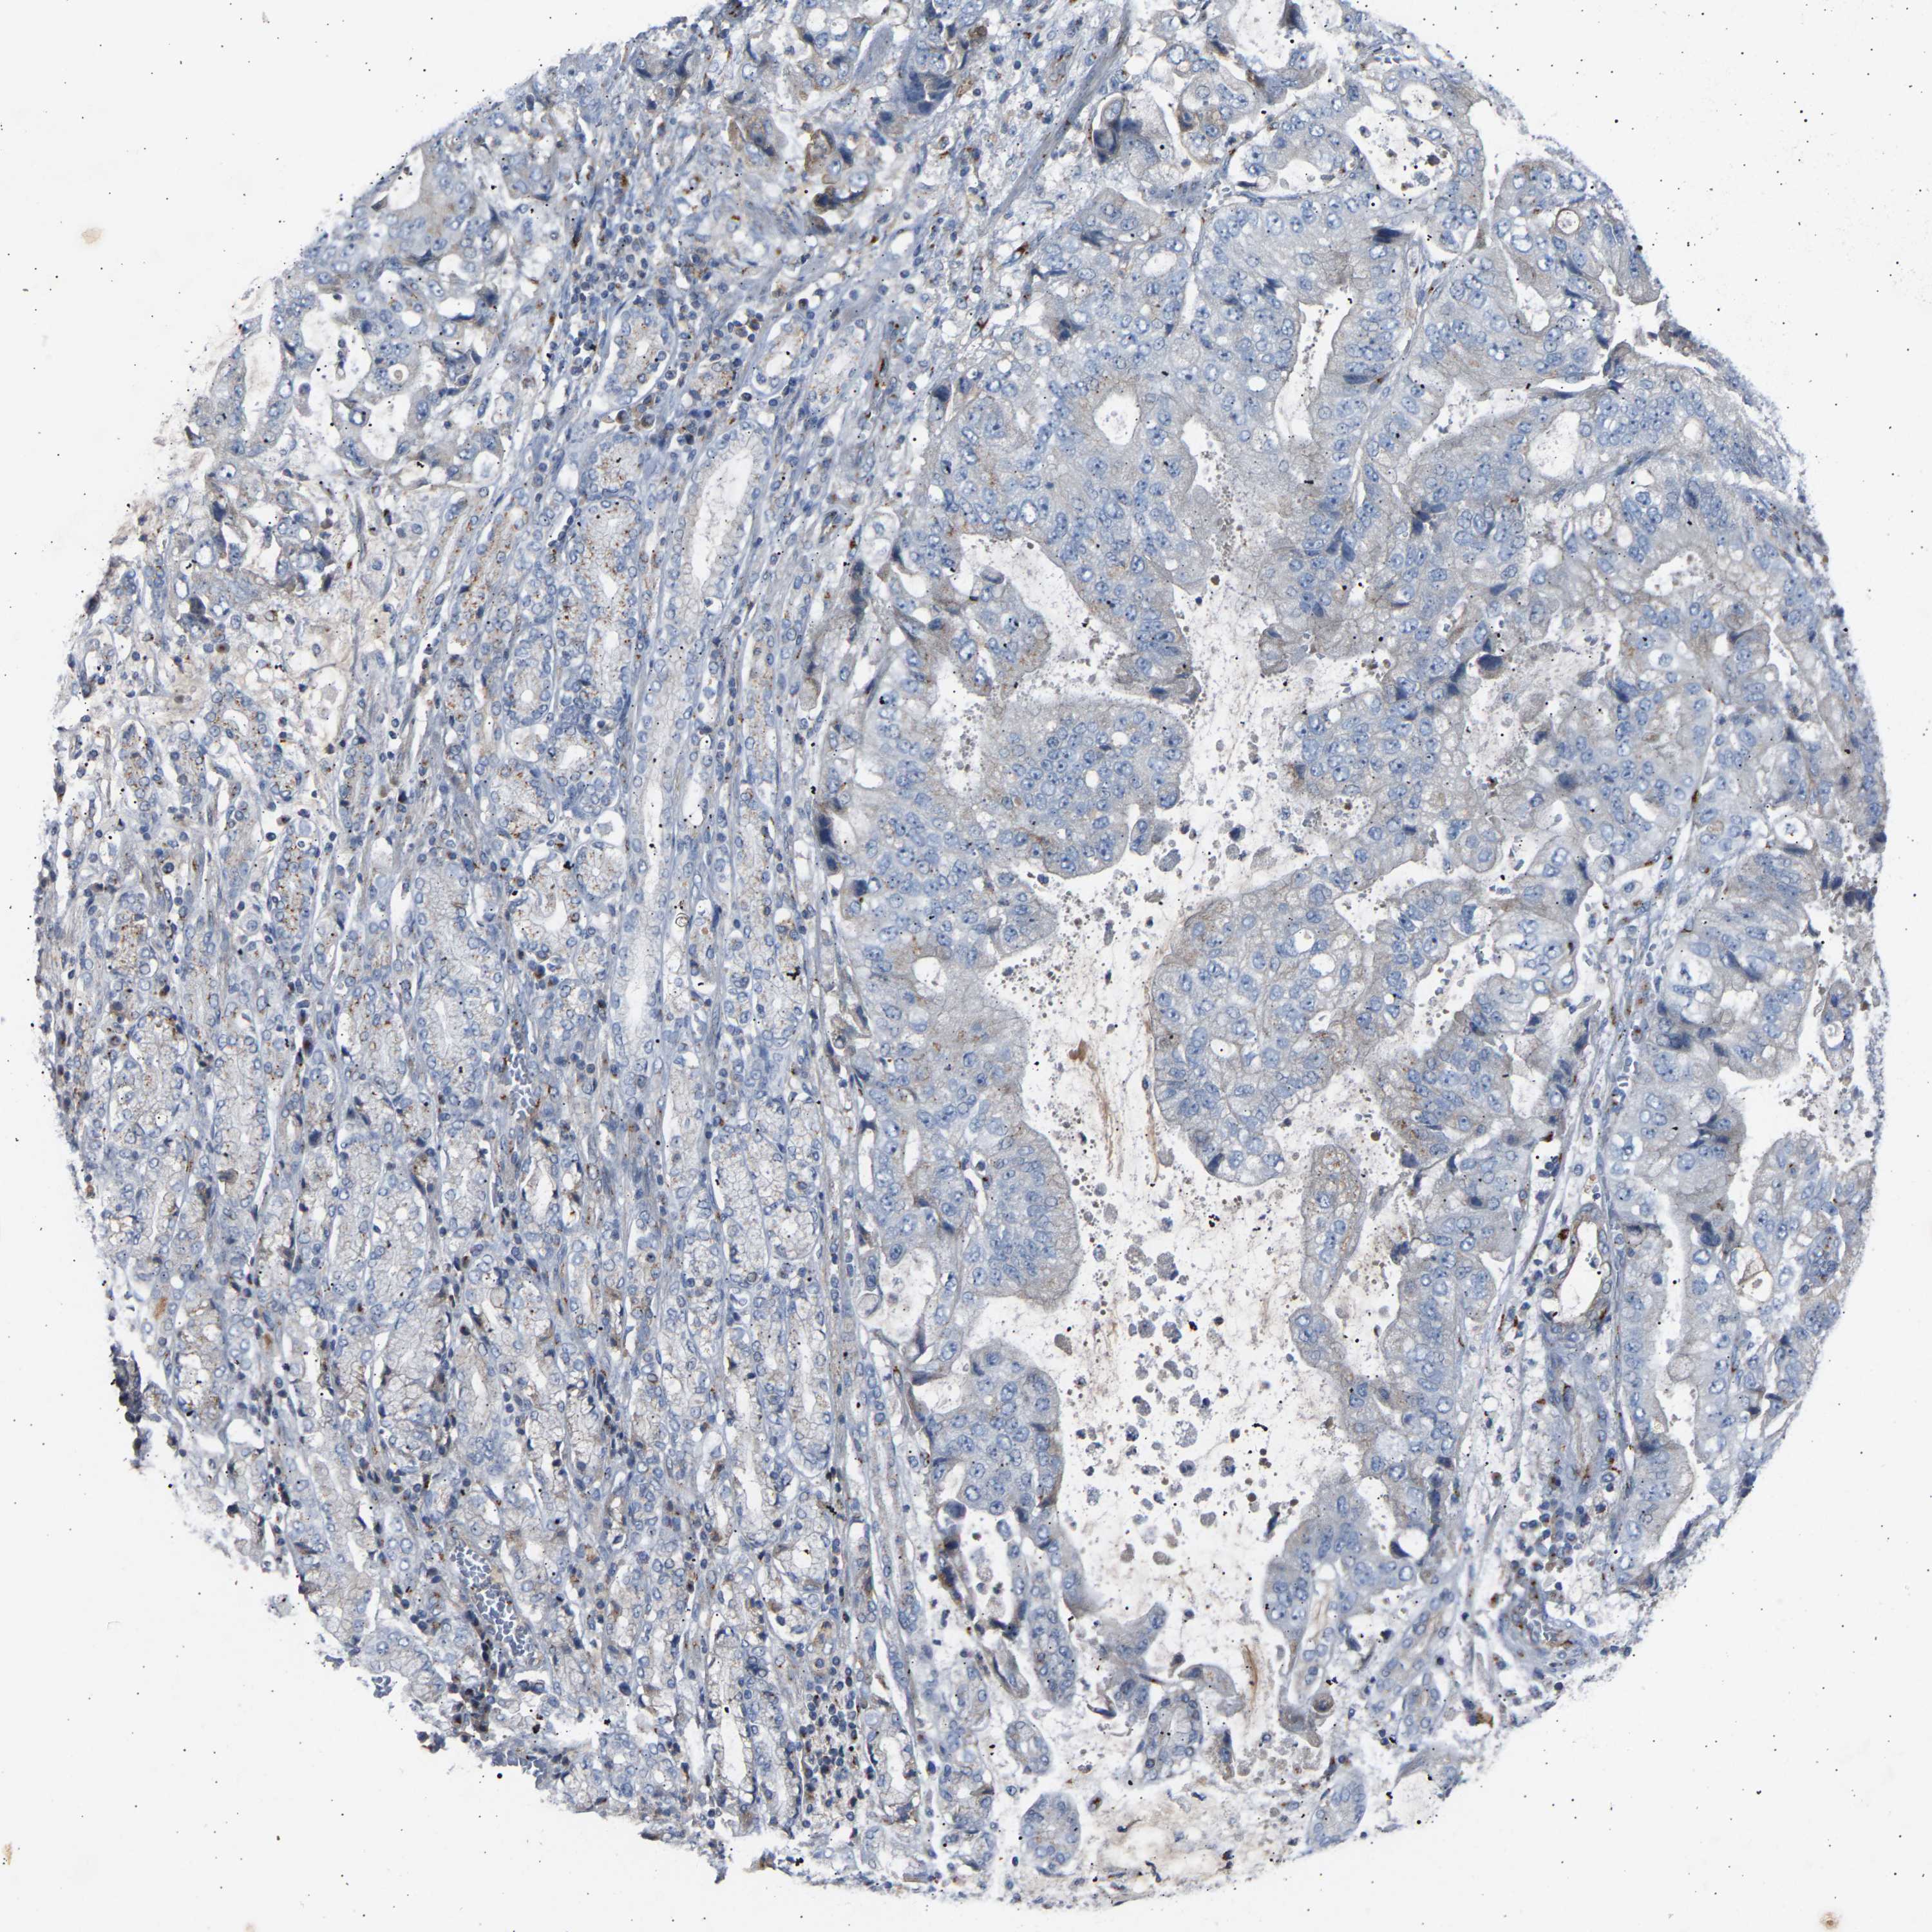

STOMACH CANCER - Protein expressioni

A mouse-over function shows sample information and annotation data. Click on an image to view it in a full screen mode. Samples can be filtered based on level of antibody staining by selecting one or several of the following categories: high, medium, low and not detected. The assay and annotation is described here.

Antibody stainingi

Antibody staining in the annotated cell types in the current human tissue is reported as not detected, low, medium, or high, based on conventional immunohistochemistry profiling in selected tissues. This score is based on the combination of the staining intensity and fraction of stained cells.

Each image is clickable and will lead to virtual microscopy that enables deeper exploration of all samples and also displays staining intensity scores, fraction scores and subcellular localization as well as patient and tissue information for each sample.

Antibody HPA020060

Staining

High

Medium

Low

Not detected

Intensity

Strong

Moderate

Weak

Negative

Quantity

>75%

75%-25%

<25%

None

Location

Nuclear

Cytoplasmic/membranous

Cytoplasmic/membranous,nuclear

Adenocarcinoma, NOS